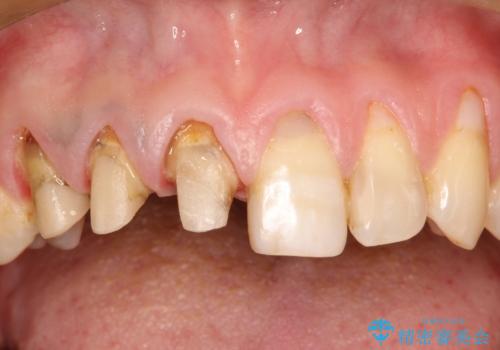

- 以前治療した上の前歯の不自然な保険のかぶせ物を自然なものにしたいとのことで来院されました。

右上の前から1番目から3番目までの歯のかぶせ物を土台から再治療することとなりました。

金属の土台を、ファイバーコアという歯根にやさしく白いものに交換して、かぶせ物をオールセラミックにしました。